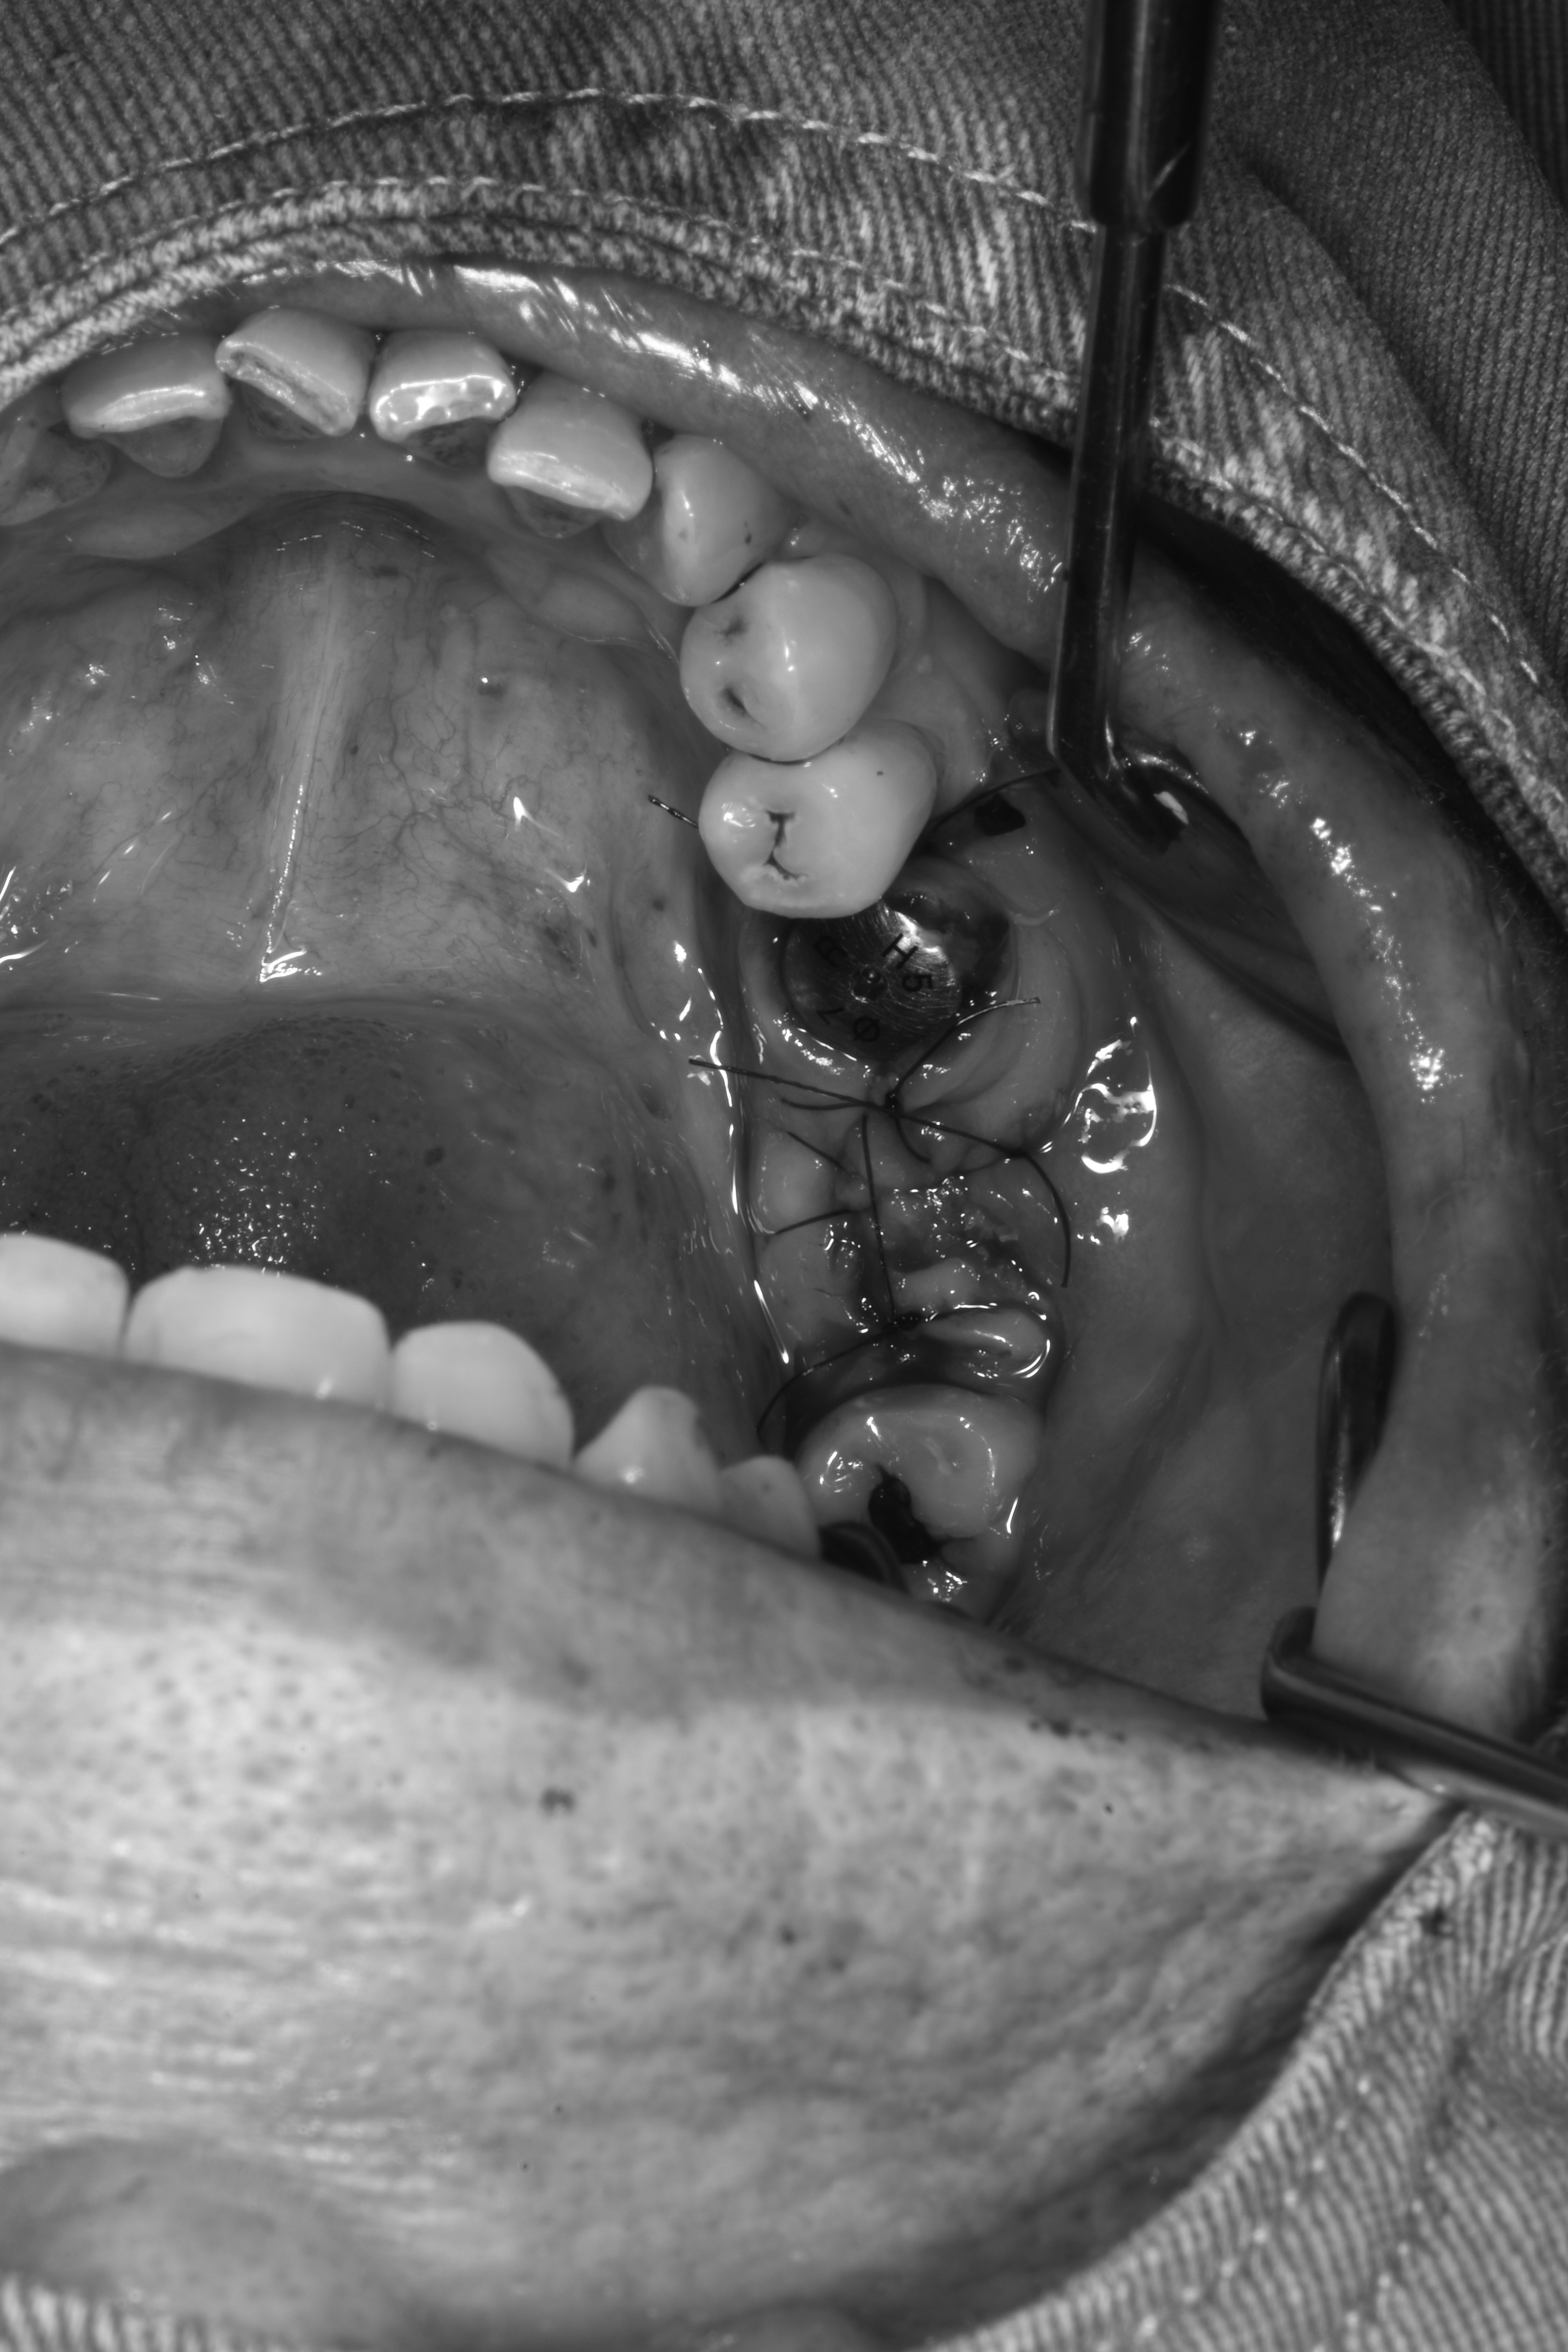

牙齦移植術(補肉)